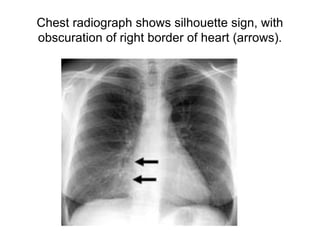

Chest radiograph shows silhouette sign, with

obscuration of right border of heart (arrows).

Chest radiograph showssilhouette sign, with obscuration of right border of heart (arrows).